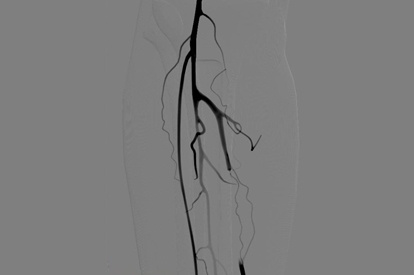

The ANGIO Mentor simulator is an essential tool for clinicians to practice and acquire the skills needed for performing endovascular interventions. Trusted by medical associations, hospitals, training centers, and the medical device industry globally, it provides trainees with realistic clinical settings to practice endovascular interventions using fluoroscopic and ultrasound guidance.

Offers true-to-life simulation of the clinical environment, including advanced imaging modalities like fluoroscopy/echocardiography, hemodynamic monitoring, medications, and interventional devices

Iliac Intervention Module

SFA Intervention Module